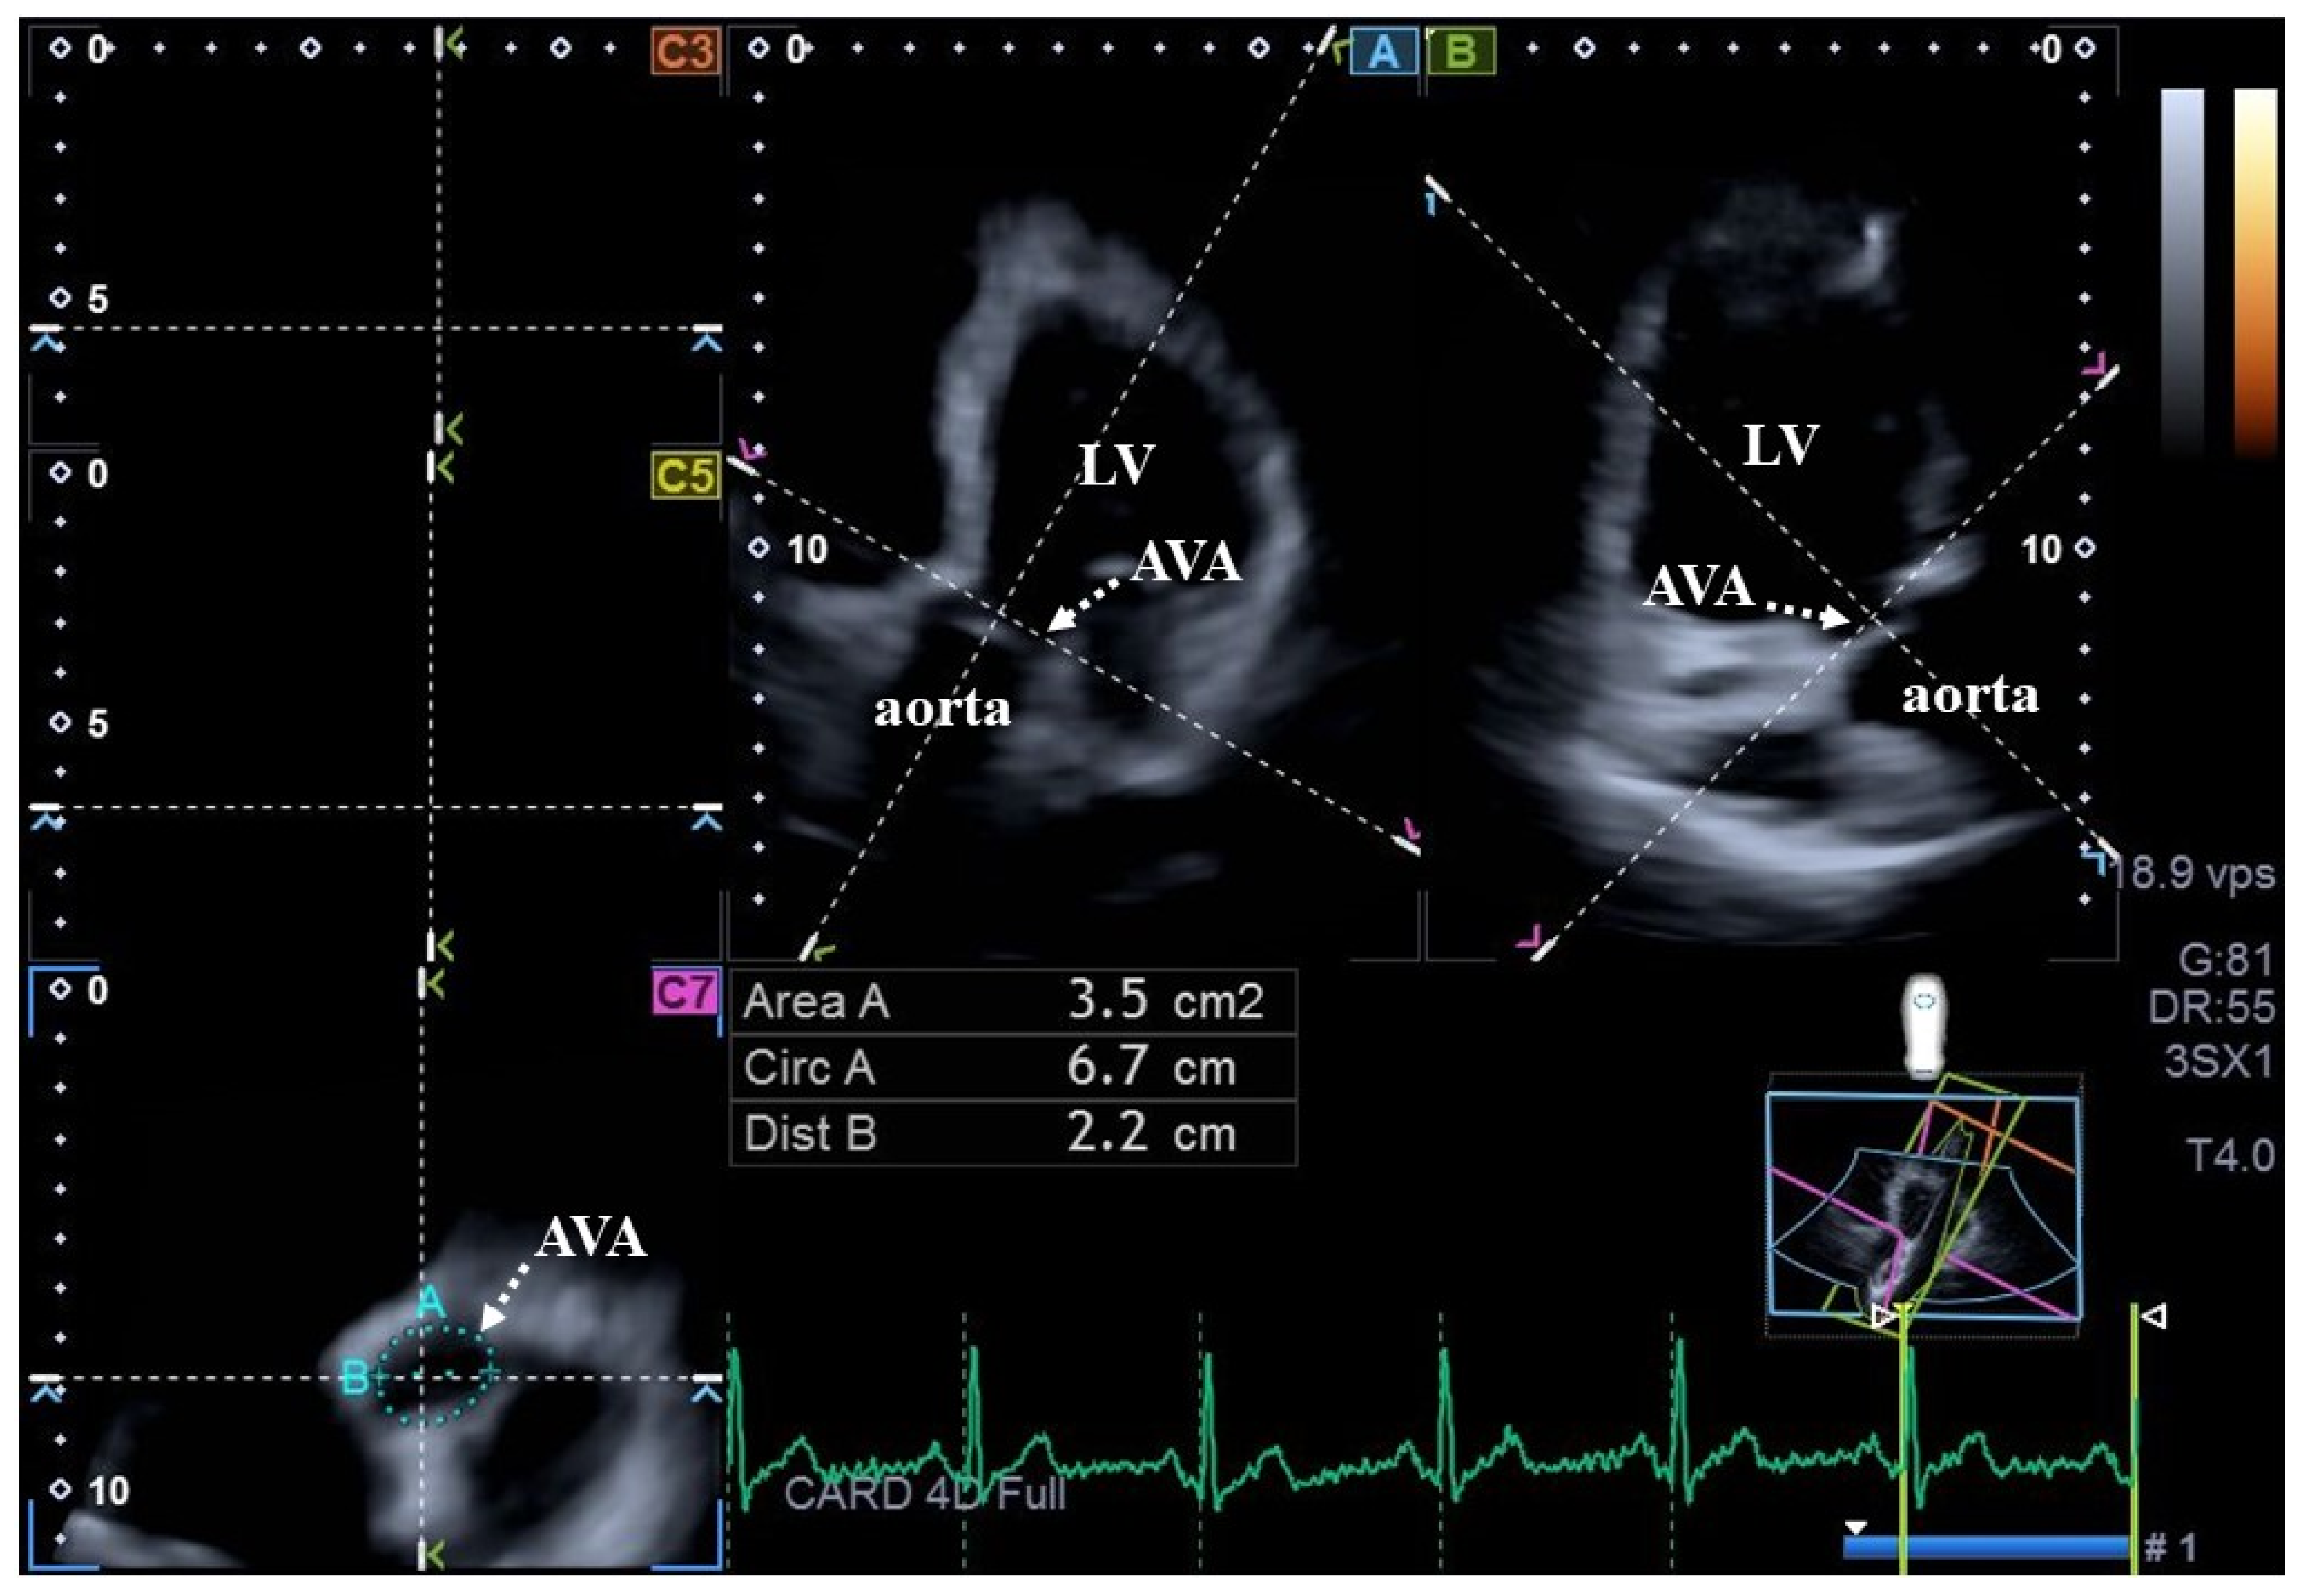

2. Subjects and Methods